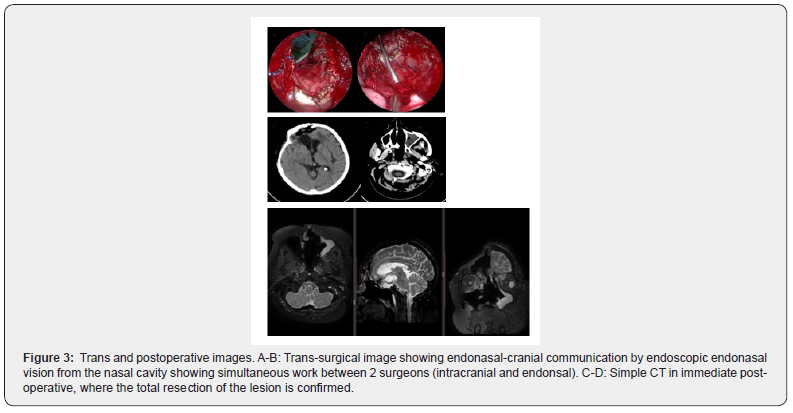

The definitive anatomopathological study showed a meningothelial meningioma (WHO grade I) with Ki-67 higher than 4% and positivity to synaptophysin protein (Figure 1, C-E). Because of the large size of the tumor mass extending into the ethmoid-sphenoidal complex, a combined simultaneous endonasal endoscopic approach-transcraneal approach through bilateral frontal craniotomy was performed. A 0-degree straight and 30-degree endoscopes 4 mm in diameter and 18 cm in length (Karl Storz Endoscopy, Tuttlingen, Germany) were used during the nasal step. A digital endoscopic HD video camera and a full High Definition (HD) flat monitor and a 300 W Xenon light source were used during the procedures. Ceftriaxone was administered via the intravenous route within 1 hour before surgery (1.5 g) and continued for 5 post-operatively (1.5 g twice a day) until nasal packing (Foley balloon) were removed. After orotracheal intubation under general anesthesia, the patient was placed supine with head fixed in the three-point Mayfield-Kees skeletal headrest and turned 10 ̊ - 15 ̊ on the horizontal plane, towards the surgeon. The head was extended 20 degrees to facilitate the anterior cranial base exposure during the endonasal approach and the frontal lobe retraction during the transcranial approach. The nasoethmoidal tumor was removed in a piecemeal fashion. After that, a wide sphenoidotomy was performing in order to expose the postero-inferior margin of the dissection and to use both optocarotid recess as landmarks. A frontotemporal incision and craniotomy was performed. A secondary incision was made in the left naso-orbital region in order to remove the facial component of the tumor. One surgeon dissected the tumor from the inferior (endoscopic) view while a second surgeon dissected the tumor from an intracranial view with a microscope. Thus, four hands, two surgeon’s technique was done (Figure 2).

The frontal sinus was approached by Draft type III sinusotomy that represents the anterosuperior margin of the dissection. The resulting skull base defect was reconstructed by using a multilayer technique with fat, fascia lata and pericranium under endoscopic visualization. A Foley catheter balloon maintained the nasoseptal flap until the fifth day postoperative when it was removed. Surgical bleeding was 900 ml and surgical time was 520 minutes. There were not intra-operative or postoperative complications. The patient was extubated in the operating room and passes the first 48 hours in Intensive Care Unit. The hospital stay was 9 days (Figure 3).